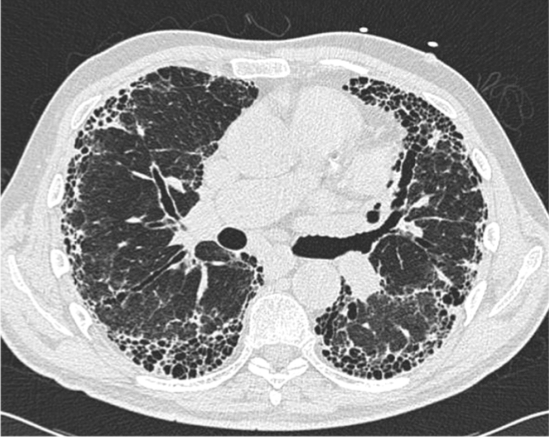

The UIP pattern of IPF on HRCT consists of ______, ______, ______, and ______

The UIP pattern of IPF on HRCT consists of sub-pleural basilar-predominant fibrosis, reticulation, honeycombing, traction bronchiectasis (not mandatory)